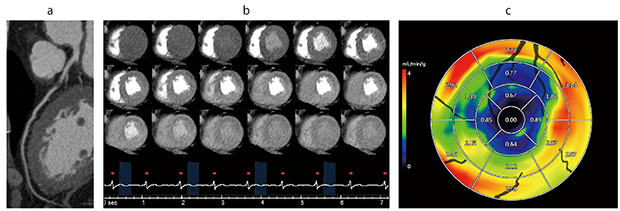

図1 ダイナミック心筋Perfusionによる包括的心臓CT

a:Coronary CTAによる冠動脈形態評価(LAD)

b:負荷ダイナミック心筋Perfusionによる心筋の定性評価(Beat Skip撮影)

c:心筋血流量(MBF)による心筋の定量評価(ワークステーション「Vitrea」)

LAD#7に高度狭窄を認める。負荷ダイナミック心筋Perfusionにて心中部前壁中隔から心尖部に灌流低下を認め、虚血を疑う。